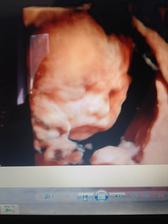

Tak sa podarilo? Pametam si ta zo snaziliek...teda aspon dufam, lebo sa mi to tu uz zlieva vsetko 😃😃😃